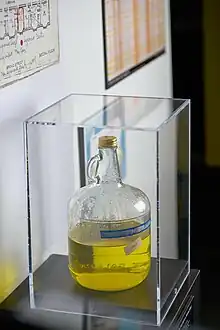

The bacteria may also be transmitted from contaminated aerosols generated in hot tubs if the disinfection and maintenance programs are not followed rigorously.[28] Freshwater ponds, creeks, and ornamental fountains are potential sources of Legionella.[29] The disease is particularly associated with hotels, fountains, cruise ships, and hospitals with complex potable water systems and cooling systems. Respiratory-care devices such as humidifiers and nebulizers used with contaminated tap water may contain Legionella species, so using sterile water is very important.[30] Other sources include exposure to potting mix and compost.[31]